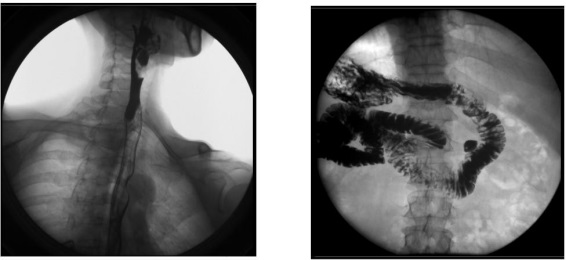

2、數(shù)字化胃腸功能:適用于胃腸道造影檢查,如食管造影、上消化道造影、全消化道造影等。

2) 肛腸科:可應(yīng)用氣鋇雙重造影和排便造影(DFG)功能,可檢查大腸的細(xì)小病變,如小息肉、早期腫瘤、潰瘍等效果良好;可檢查肛管炎、恥骨直腸肌綜合癥、骶骨部畸胎瘤、直腸前突、直腸內(nèi)套疊、肛門直腸損傷和異物等檢查。

3、其他造影:適用于各種普通及特殊造影,如口服膽囊造影、靜脈膽道造影、T 管造影、逆行胰膽管造影(ERCP)、靜脈腎盂造影(IVP)、子宮輸卵管造影等。

2) 肝膽外科:膽管手術(shù)后,切開膽總管植入 T 管引流,起支撐作用,防止術(shù)后膽總管狹窄,術(shù)后應(yīng)用胃腸機(jī)進(jìn)行膽管造影(T 管造影),檢查膽道內(nèi)有無殘留結(jié)石及異物,是否通暢無阻, 對手術(shù)進(jìn)行評估;